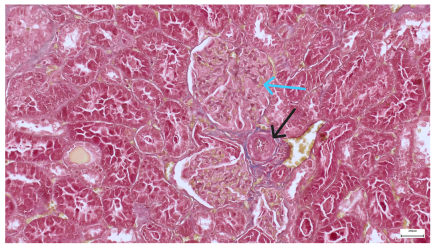

| 4.7. Trichrome Masson stain, magnification 100×, scale 200 microns. Renal corpuscle with relatively increased thickness of the glomerular basal membrane (black), renal corpuscular congestion, mesangial expansion, unequal glomerular dimensions (blue). Group IV diabetic-and-obese specimens. | 4.8. Hematoxylin and Eosin stain, 100× magnification, scale 200 microns. Tubule “thyroidisation” (black) denoting the presence of eosinophilic material inside tubular lumen, the flattening of tubular wall cells as a consequence of glomerular partial or total sclerosis, significant hypercellular matrix environment in glomerulus (blue). Group IV diabetic-and-obese specimens. |

| 4.9. Trichrome Masson stain, magnification 100×, scale 200 microns. Arterial wall thickening is regarded as hyalinization (black), corpuscular congestion and start of segmental sclerosing (blue). Group IV diabetic-and-obese specimens. | 4.10. Hematoxylin and Eosin stain, 100× magnification, scale 200 microns. Mesangial cell expansion and irregular glomerular dimensions. Group IV diabetic-and-obese specimens. |